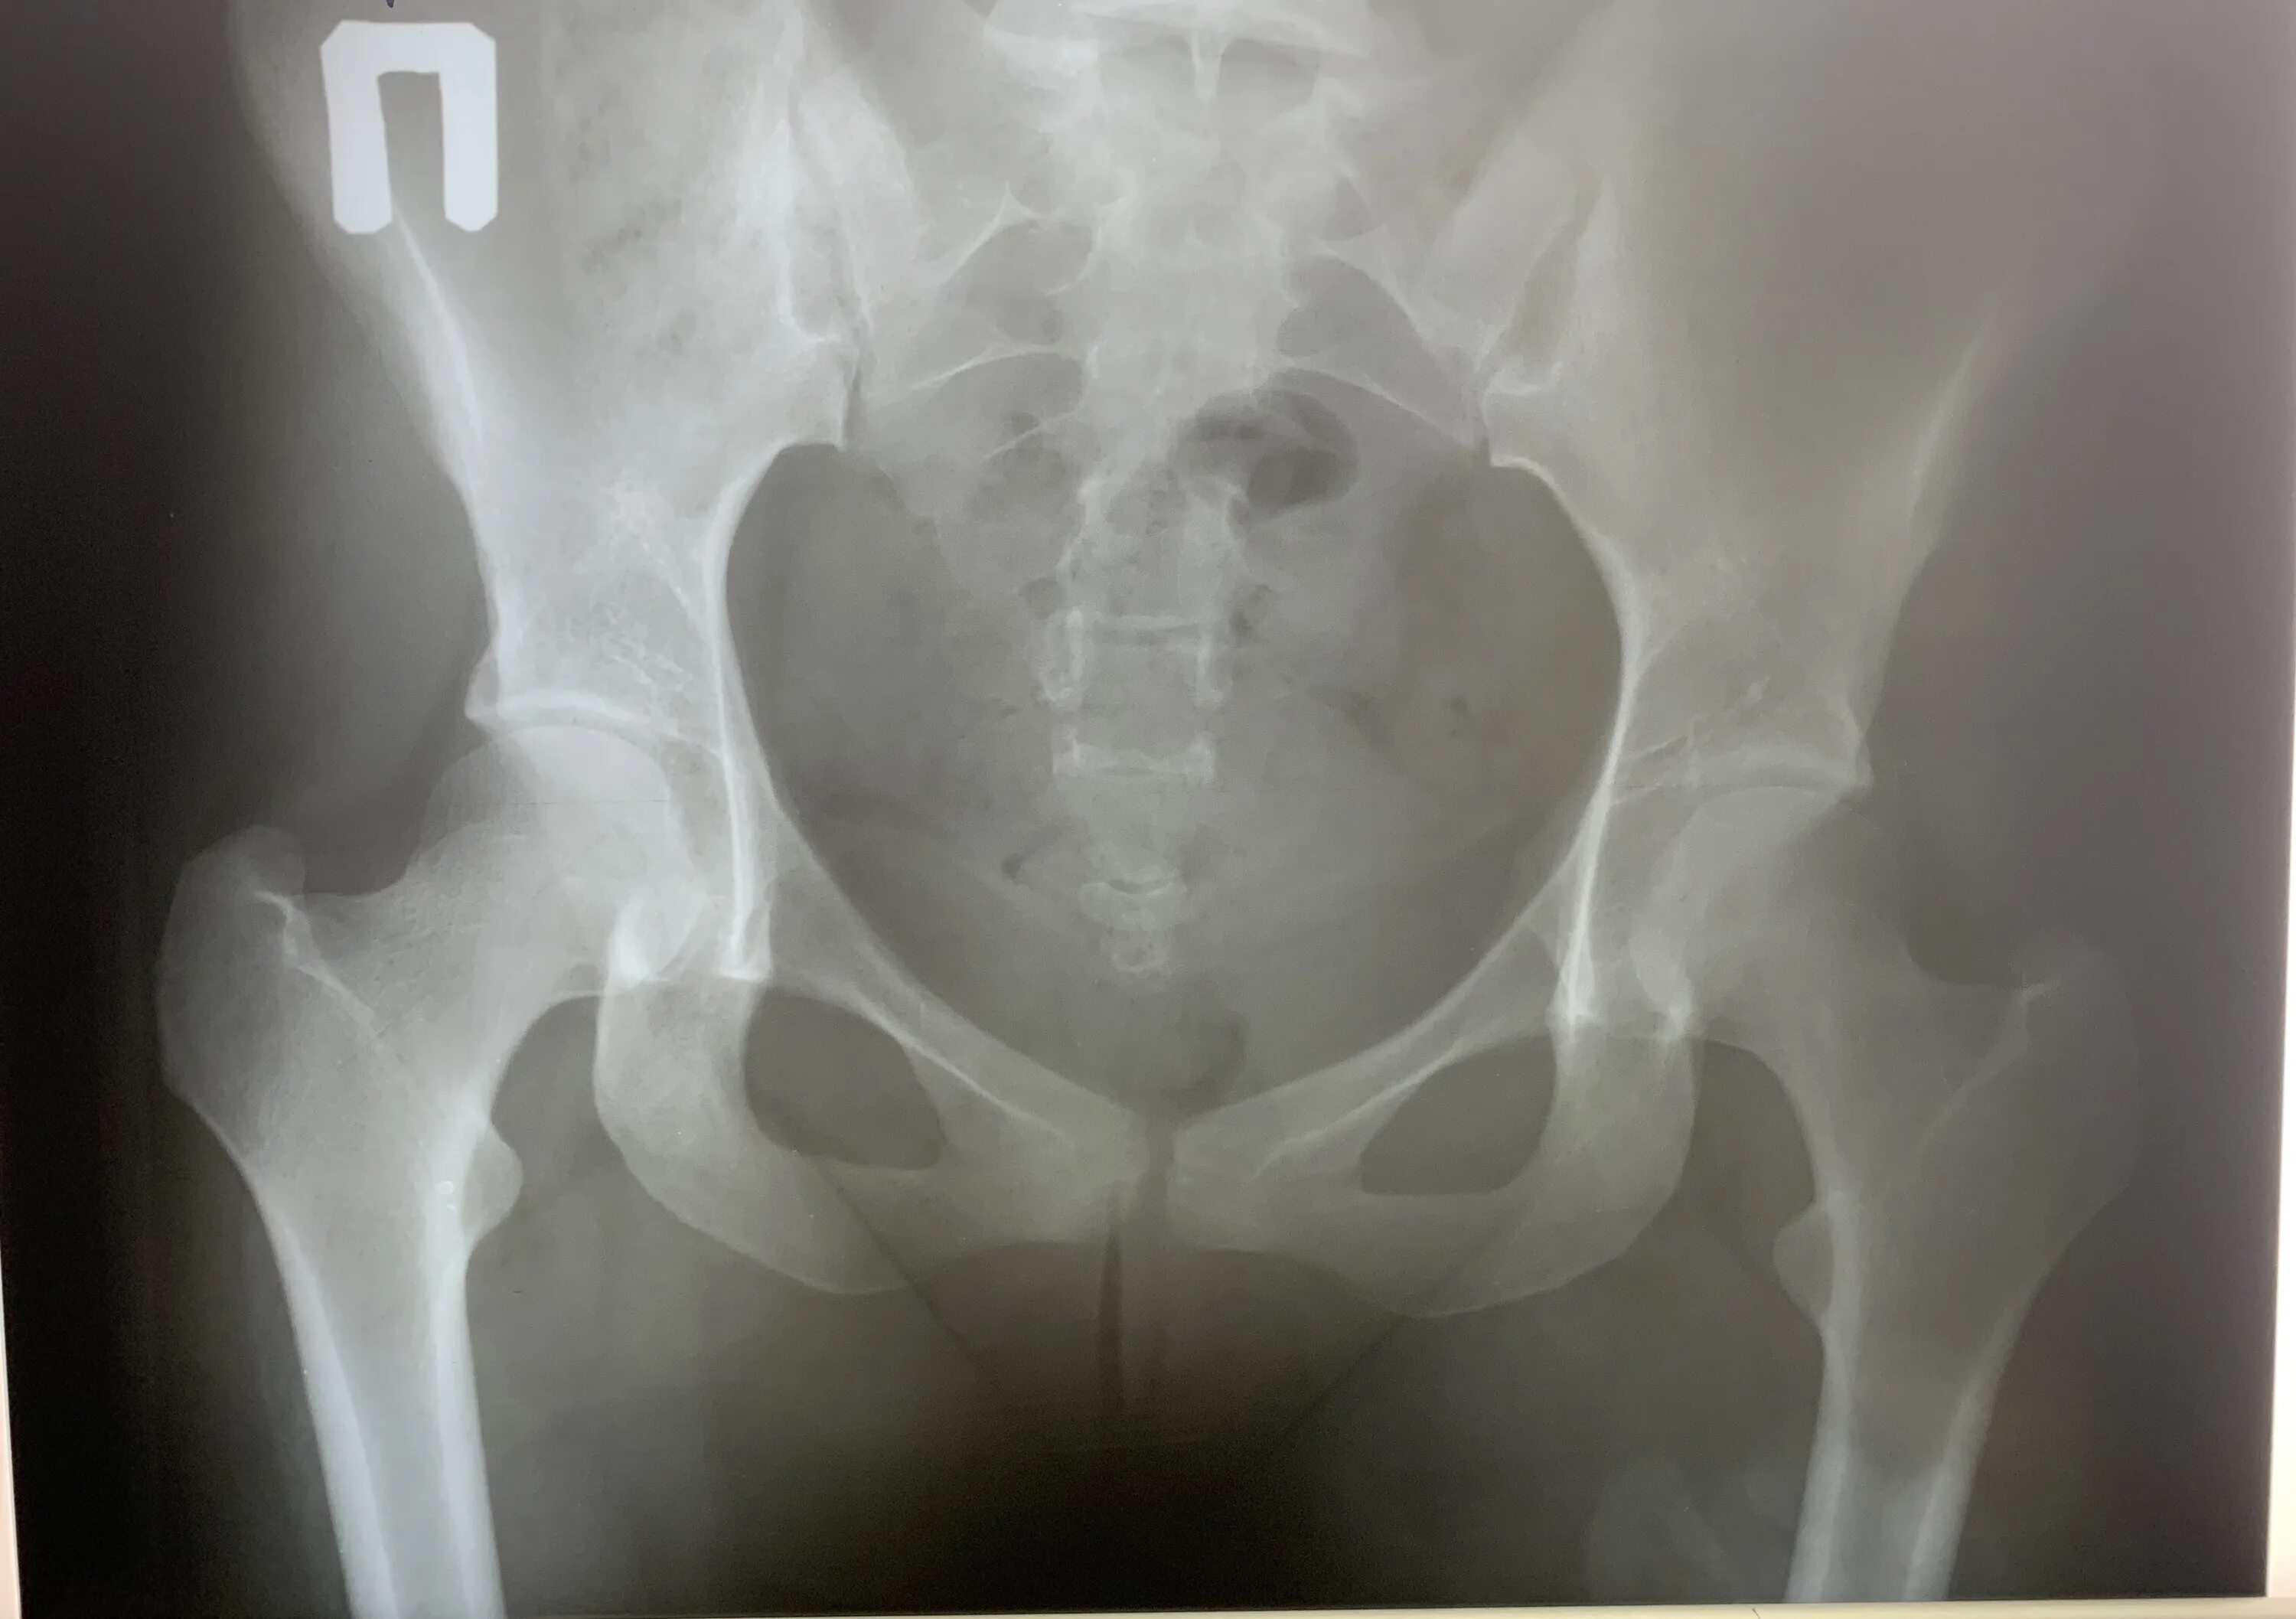

Разрыв крестцово подвздошного сочленения